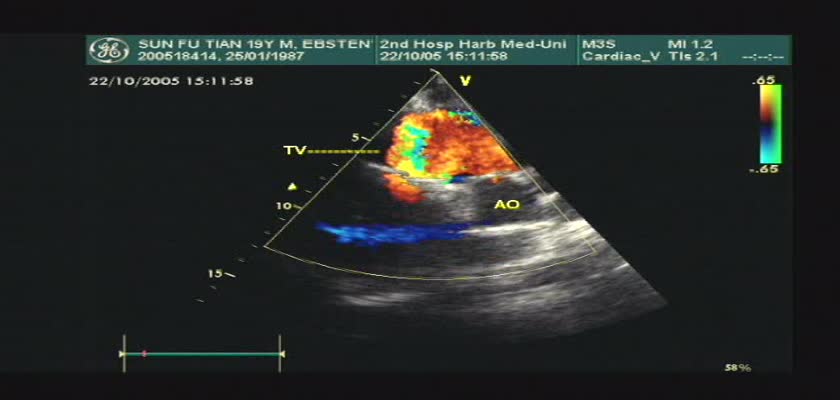

先天性心脏病超声诊断-先天性心脏病超声诊断视频17